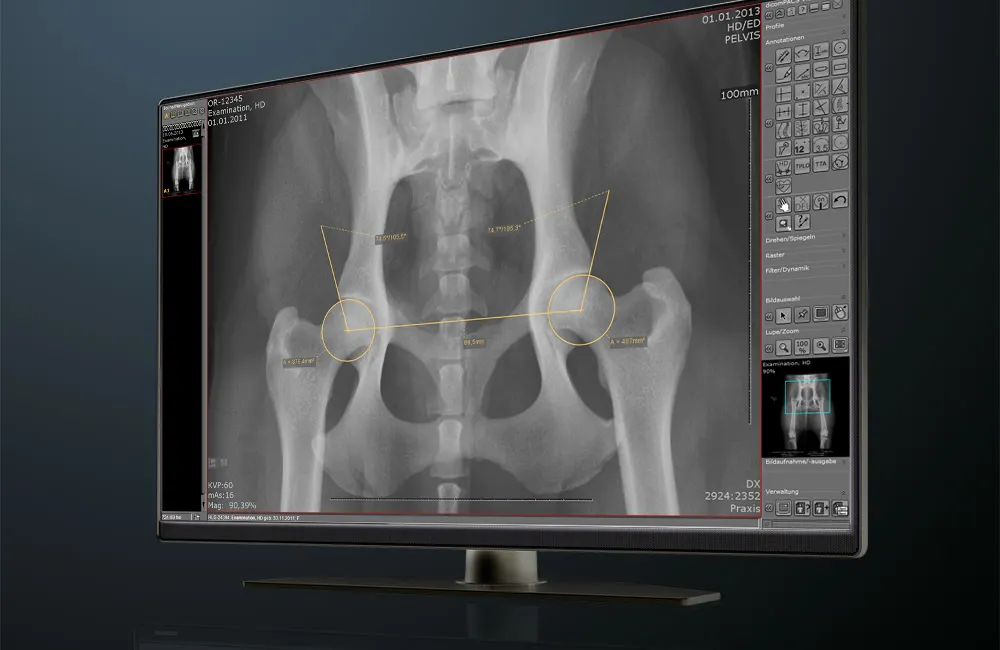

dicomPACS®DX-R is the heart of our OR 4Vet systems – featuring smart operation, AI support, dynamic X-ray, and wireless control – perfectly tailored to modern veterinary medicine. A fast and reliable acquisition and diagnostic software that optimally supports you in everyday practice.